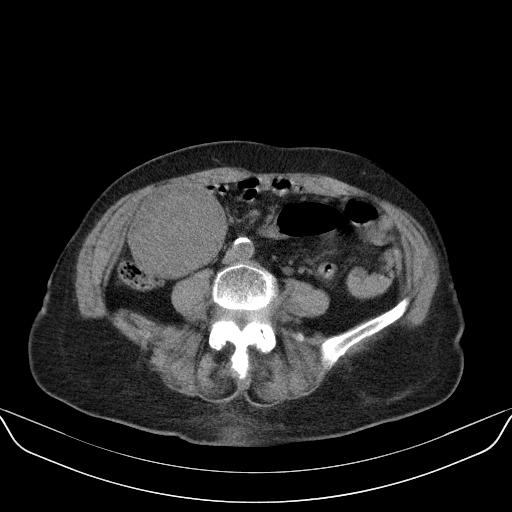

以下是引用林建春在2010-3-11 17:21:00的发言:[br]病变边界较清晰,看见明显包膜,考虑良性占位性病变。[br][br]期待病理结果!

以下是引用yuhongjun在2010-3-12 6:32:00的发言:[br]回肠末端间质瘤,不除外阑尾粘液囊腺瘤,臀部注射性肉芽肿钙化. [br] [br]